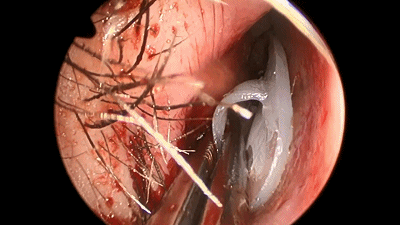

▼手术完成后,双侧鼻腔对称填塞膨胀海绵(下图示Doyle夹板),将双侧切口的粘膜复位。

▼鼻中隔黏膜切口也可缝合2~3针,防止黏膜退缩、软骨暴露而延缓伤口愈合及结痂。

![]()